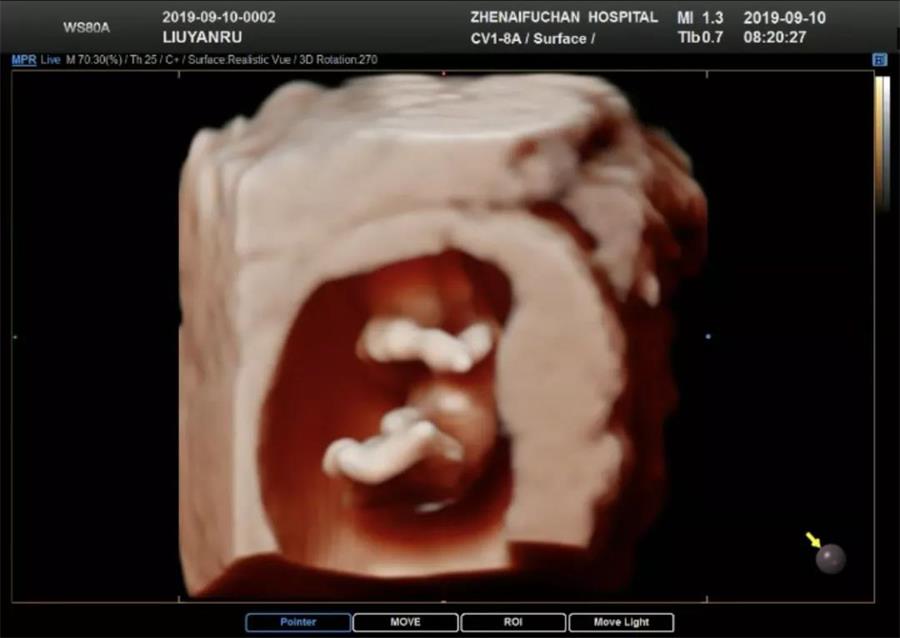

5D彩超为NT筛查护航

珍爱妇产省内独家引进5D彩超,用于NT筛查,360度立体呈现胎儿宫内发育情况。比大家所熟知的四维彩超清晰度更高,诊断范围更全面。

能够更多方位、多角度地观察宫内胎儿的生长发育情况。在检查同时,宝爸妈们还可以像观赏电影那样,看到他乖巧的模样及一举一动,还可以把宝宝视频存储到手机里永久保存。